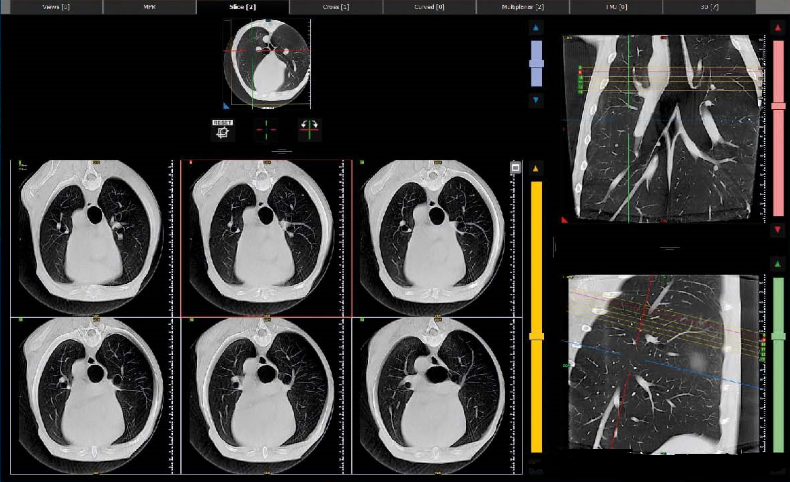

NNT软件的先进功能可以覆盖多个医学专业,特殊的重建窗口响应每个部门的不同需求。所有检查都完全兼容 DICOM 格式:它们可以通过 NNT 查看器共享或以 1:1 的比例打印。与 NewTom 采用的现代系统的出色连接性和集成性。工作流程、临床和诊断活动变得更加容易和高效。简单的 3D 显示界面使与宠物主人的交流变得更加容易,即使是不熟悉影像阅读的观众也能清楚地了解患者的病情。可以选择软组织和骨组织的单独或叠加成像。3D 测量、气道模拟和切片工具也可用于获取感兴趣体积的横截面。用于研究牙弓的专用界面可生成横截面和轴向重建,并通过多平面重建生成与牙科全景图相当的图像。它还可以为冠状面和矢状面生成特定的重建。对于所有这些图像,可以独立管理厚度、亮度和对比度。NNT 软件有一个专门的窗口,用于骨骼结构的双边成像,例如颞下颌关节和较小的关节。观察窗在中间显示轴向图像,左侧和右侧显示专用重建;在底部中央区域,显示了 3D 效果图。